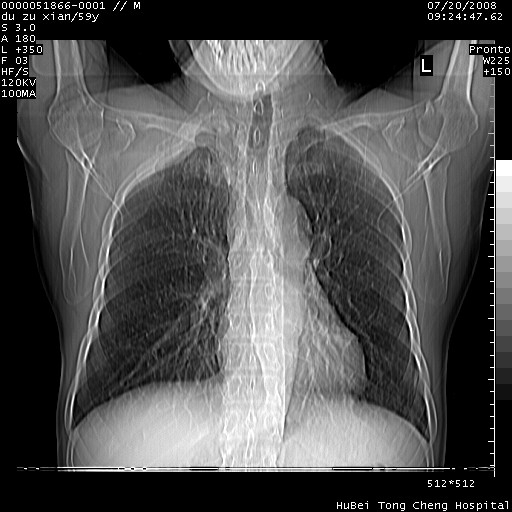

以下是引用宇宙ct在2008-8-25 23:21:00的发言:[br]右肺周围性肺癌并肋骨转移,纵隔淋巴结转移。

以下是引用zsl6918在2008-8-25 22:40:00的发言:[br]右肺周围性肺癌并肋骨转移,纵隔淋巴结转移。

以下是引用zy_zj在2008-8-26 15:24:00的发言:[br]单从病变本身,我倾向良性炎性病变,但肋骨转移了,所以说是考虑右肺周围性肺癌并肋骨、纵隔淋巴结转移可能性大。